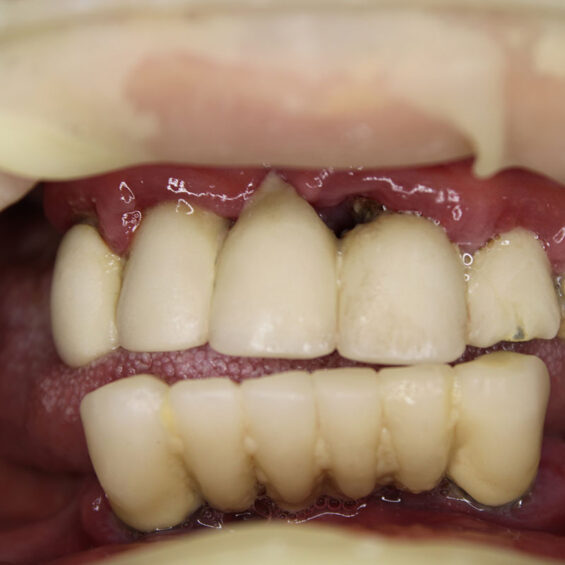

Decidí acudir ya que no aguantaba el dolor que tenía, no podía comer y me afectaba en el día a día. Cuando Susana me exploró, inmediatamente supo lo que necesitaba. Los dientes que me quedaban no podían aguantar más tratamientos Planificó la extracción de todos ellos y el tratamiento de All On Four superior y 6 implantes mandibulares . Con colocación inmediata de dientes el mismo día que me los extrajo y colocó los implantes. Entrar y salir con dientes.

Valentín ha sido en todo momento un paciente comprensivo y colaborador. Su cirugía requirió una planificación muy precisa, pues se trataba de implantes postextracción y carga inmediata. Finalmente, una rehabilitación fija sobre implantes con todos los criterios que exigía.

- Rehabilitación completa sobre implantes